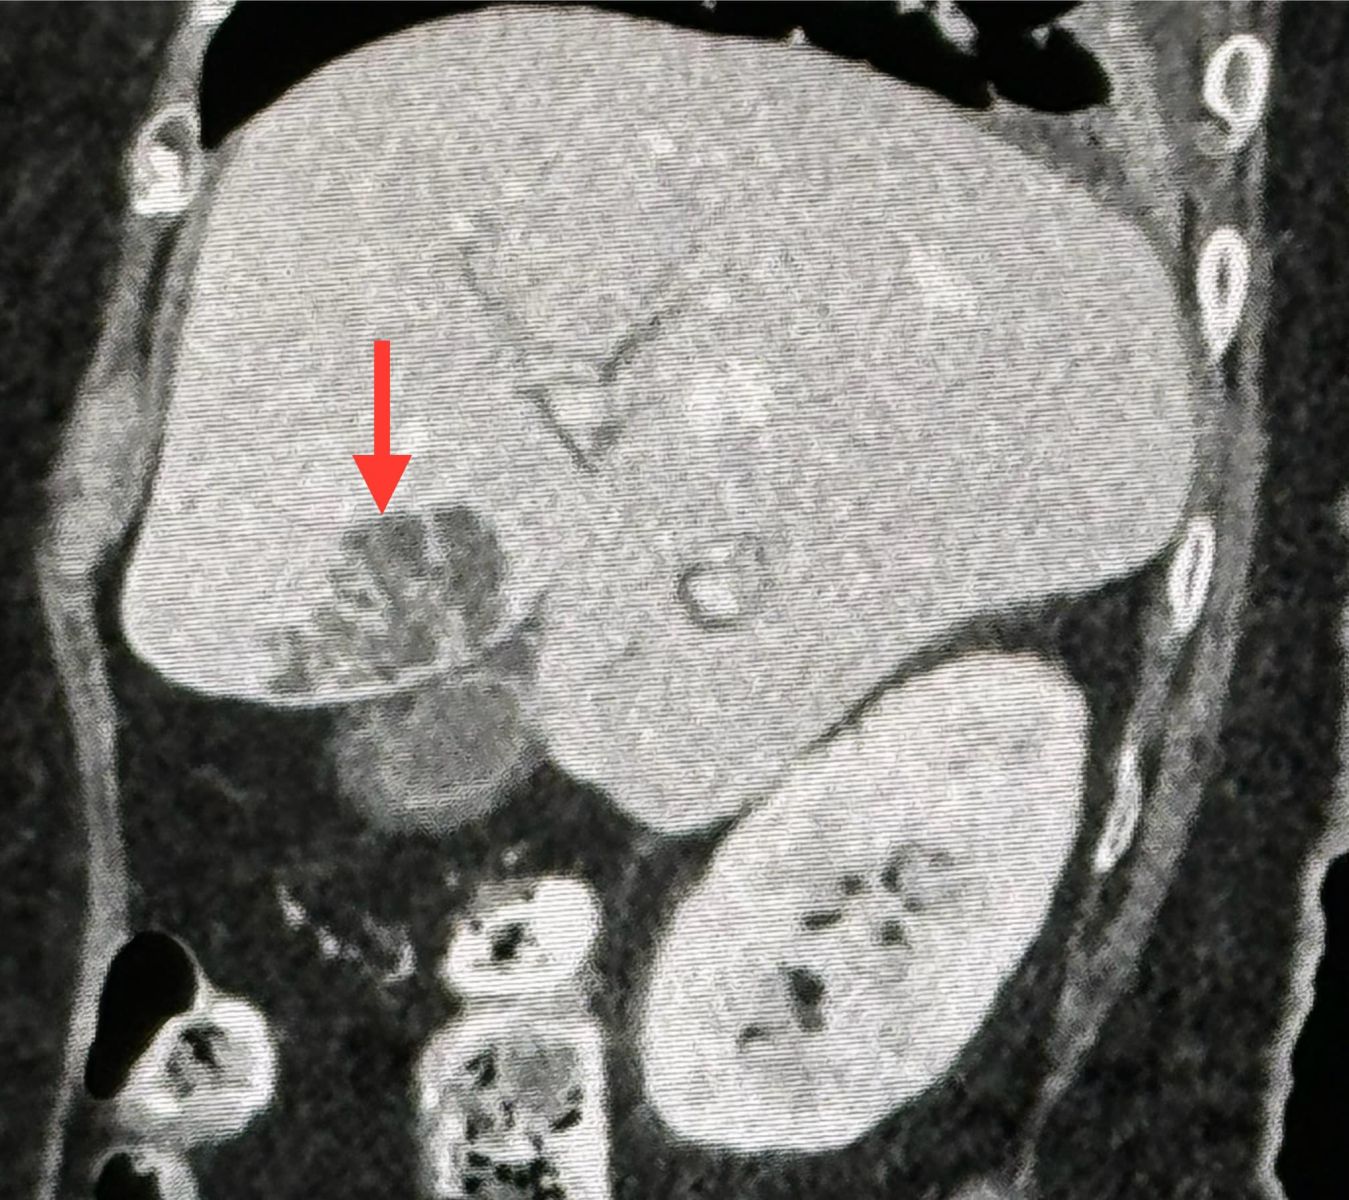

หมอมนูญ เปิดเผยด้วยว่า ผลตรวจร่างกาย มีไข้สูง ฟังปอดปกติ คลำท้องไม่เจ็บ ตับไม่โต เจาะเลือด เม็ดเลือดขาวในเลือดสูง 29,300 ค่าเอนไซม์ตับสูงเล็กน้อย SGOT 87, SGPT 73 ทำอัลตราซาวด์ช่องท้องด้านบน พบก้อนในตับข้างซ้ายขนาด 2.8 × 2.4 × 2.4 เซนติเมตร ส่งเลือดเพาะเชื้อ ขึ้นเชื้อแบคทีเรีย Klebsiella pneumoniae เอกซเรย์คอมพิวเตอร์ช่องท้อง 2 วันต่อมา พบก้อนขนาด 3.3 × 3.3 × 2.8 ซม.ในตับข้างซ้าย เข้าได้กับฝีในตับ

แพทย์วินิจฉัยว่า ป่วยเป็นฝีในตับ จากเชื้อแบคทีเรีย Klebsiella pneumoniae และติดเชื้อในกระแสเลือด ทำให้ช็อก ความดันต่ำ การรักษาให้น้ำเกลือ ยากระตุ้นความดันโลหิต และ ยาปฏิชีวนะ ceftriaxone (ทดสอบแล้วในห้องปฏิบัติการว่าเชื้อตัวนี้ไวต่อยา) ทางหลอดเลือดดำ ได้ทำการเจาะหนองจากฝีในตับผ่านทางหน้าท้อง ได้หนอง 2 ซีซี ส่งหนองเพาะเชื้อขึ้นเชื้อ Klebsiella pneumoniae ตัวเดียวกับในเลือด